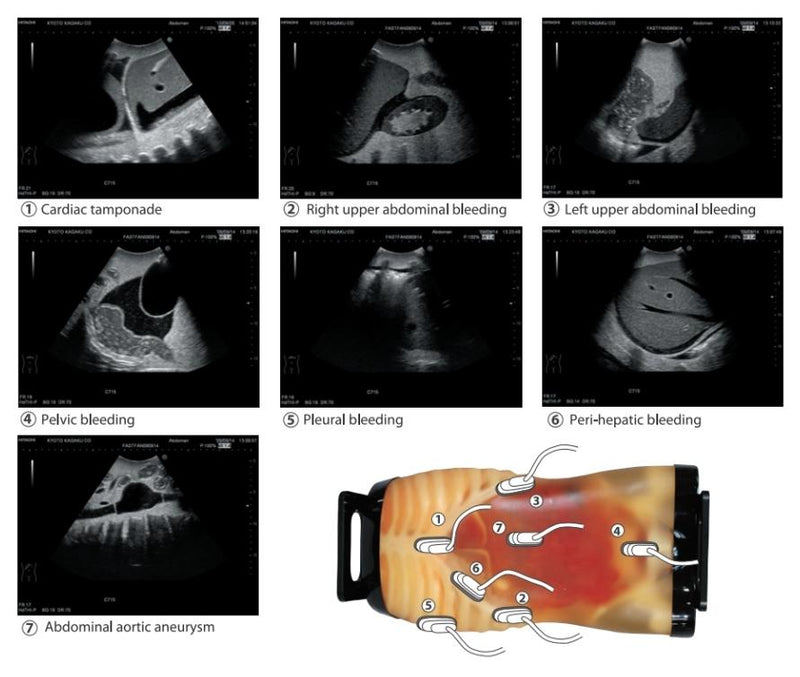

This phantom has been developed to provide simulated training in FAST (Focused Assessment with Sonography for Trauma) ; an ultrasound examination directed at identifying the presence of free intraperitoneal or pericardial fluid in the traumatic patients, which allows detecting the possible cause of shocks such as mass hemothorax, intraperitoneal hemorrhage or cardiac tamponade.An innovative phantom for repetitive training of FAST as an adjunct to the ATLS primary survey.

Training Items:

- FAST procedure: International hemorrhage at perihepatic, perisplenic, pelvis and pericardium area.

- Spnography for acute patients: Internal hemorrhage at pericardial, bilateral chambers as well as intra-abdominal hemorrhage around the liver, the spleen and the urinary bladder. Pathologies including cholecystitis, an aortic aneurysm, a lesion on the colon.

- FAST/ Cardiac Tamponade, Right Upper Abdominal Bleeding, Perisplenic Hemorrhage, emorrhage at Rectovesical Area

- Acute abdomen/Inflammation of the Gallbladder, Aneurysm, Appendicitis, Diverticulitis

- Lung / Heart / Diaphram / Liver / Kidney / Spleen / Pancreas / Colon / Bladder / Rectum / Vena cava / Aorta / Sacrum